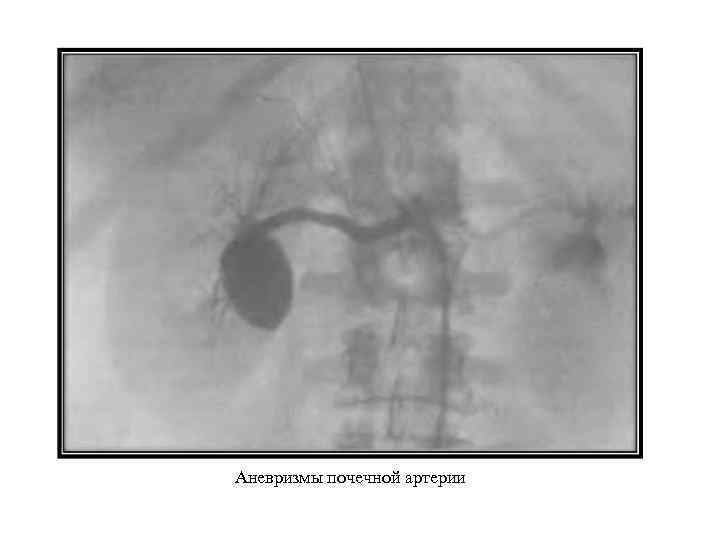

Аномалии почечных сосудов Аномалии количества: солитарная почечная артерия; сегментарные почечные артерии (двойная, множественные). Аномалии положения: поясничная; подвздошная; тазовая дистопия почечных артерий. Аномалии формы и структуры артериальных стволов: аневризмы почечных артерий (одно- и двусторонние); фибромускулярный стеноз почечных артерий; коленообразная почечная артерия. Врожденные артериовенозные фистулы. Врожденные изменения почечных вен: аномалии правой почечной вены (множественные вены, впадение вены яичка в почечную вену справа); аномалии левой почечной вены (кольцевидная левая почечная вена, ретроаортальная левая почечная вена, экстракавальное впадение левой почечной вены).

Аномалии почечных сосудов Аномалии количества: солитарная почечная артерия; сегментарные почечные артерии (двойная, множественные). Аномалии положения: поясничная; подвздошная; тазовая дистопия почечных артерий. Аномалии формы и структуры артериальных стволов: аневризмы почечных артерий (одно- и двусторонние); фибромускулярный стеноз почечных артерий; коленообразная почечная артерия. Врожденные артериовенозные фистулы. Врожденные изменения почечных вен: аномалии правой почечной вены (множественные вены, впадение вены яичка в почечную вену справа); аномалии левой почечной вены (кольцевидная левая почечная вена, ретроаортальная левая почечная вена, экстракавальное впадение левой почечной вены).

Фибромускулярный стеноз левой почечной артерии

Фибромускулярный стеноз левой почечной артерии